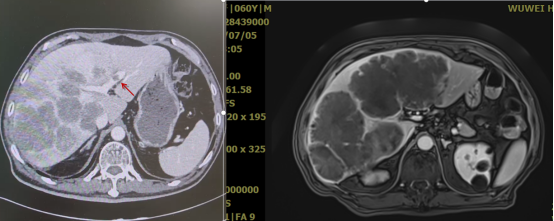

【病例二】肝癌多发肝内转移的重(碳)离子治疗

患者雷某,女,55岁,陕西籍。病史:患者于2022年12月2日体检时行腹部MR示:肝右叶占位性病变,大小约5.0cm×4.8cm,肝内多发结节,大小约1.0~1.8cm,多考虑肝癌。肿瘤标志物示:AFP 390.80ng/ml。2022年12月7日就诊于我院,行PET-CT示:肝SⅧ段稍低密度肿块,大小约41.5×40.2×32.8mm,代谢同肝脏本底,结合外院MRI,多考虑高分化肝Ca。腹部MR示:肝内多发占位,考虑肝Ca并肝内转移。行超声引导下经皮肝肿物穿刺活检术,术后病检示:肝细胞癌,中分化。免疫组化结果显示:CD34(血管+),Glypican-3(+),Hepatocyte(+),Ki-67(index约5%),CK8/18(+),CK19(-),CK7(-)。诊断:肝恶性肿瘤、肝细胞癌(中分化)、rcT2N0M0 Ⅱ期、BCLC分期:B(中期)、CNLC分期:Ⅱb期、Child-Pugh分级:A级、KPS评分:90分。于2022年12月21日至2023年1月3日给予肝脏肿物重(碳)离子治疗。

wuwei

【病例提供医生:张雁山 科室:放疗中心一科】